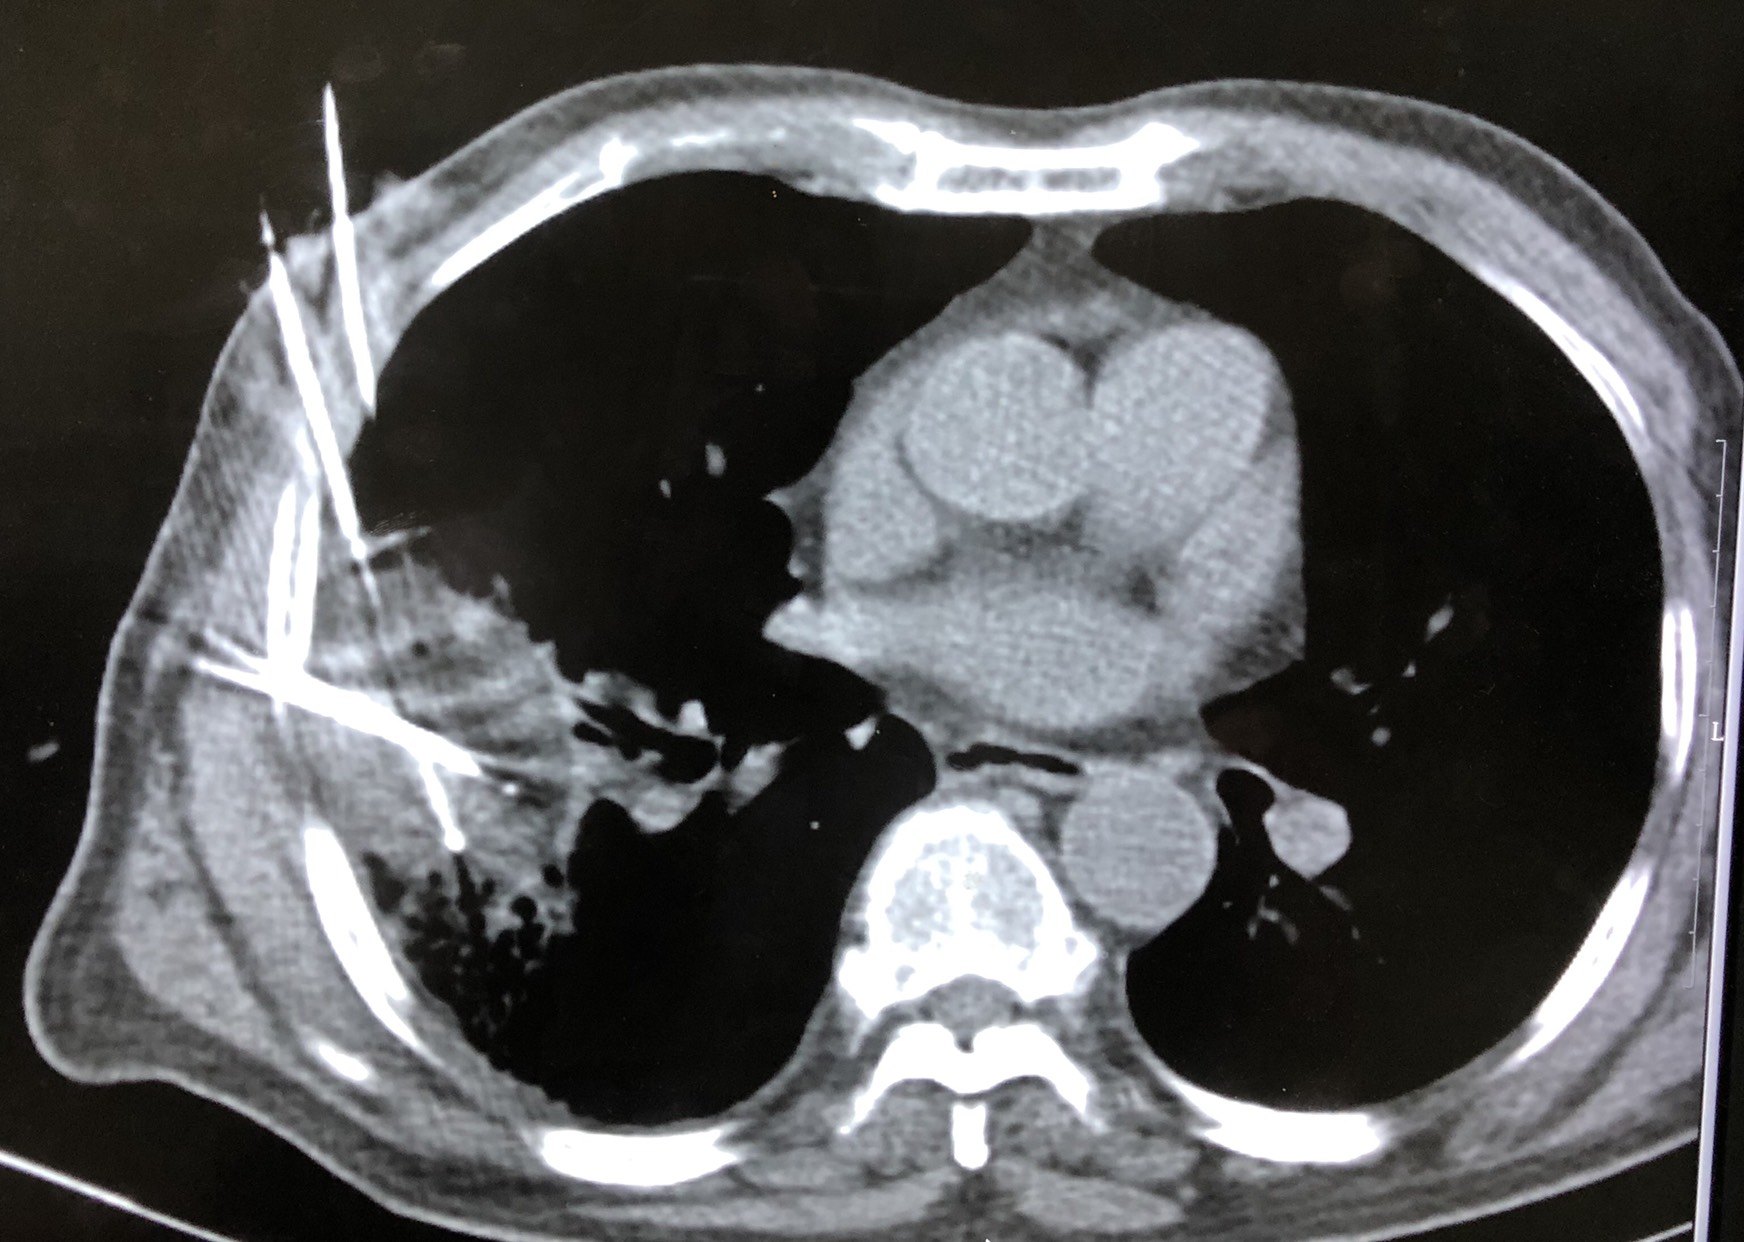

图3半月后复查,肿瘤基本坏死,呈空洞改变。